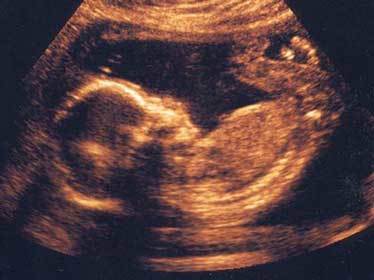

Em bé "tự sướng" trong bụng mẹ

Cả bé trai và bé gái đều có những hành động thủ đâm trong dạ con của mẹ, thậm chí các bé trai còn có thể cương dương.

Em bé tự sướng trong bụng mẹ (nguồn: Oddee) |